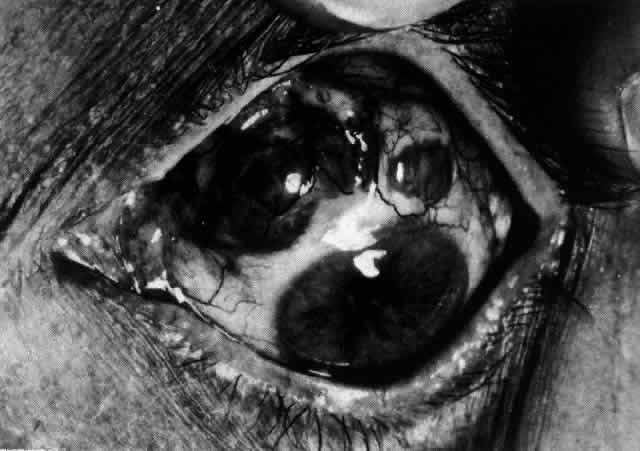

Necrotizing Anterior ScleritisdWithout Adjacent Inflammationd(Scleromalacia Perforans)

Necrotizing anterior scleritis without adjacent inflammation appears to be a well-defined condition with little relation in clinical features to necrotizing scleral disease, even though the pathology is similar and the final result is the same. Scleromalacia perforans is characterized by the almost total lack of any symptoms. It occurs almost exclusively in patients with long-standing polyarticular rheumatoid arthritis, the majority of whom are female (Figs. 49 and 50; Color Plate 1E).

Fig. 49. A white necrotic plaque developing in an area of sclera with practically no surrounding inflammation in a 60-year-old woman who had had Crohn's disease for 17 years.

Fig. 50. Scleromalacia perforans after treatment. The very thin sclera is covered by conjunctiva only and a few remaining large blood vessels. (Courtesy of Mr. HE Hobbs)

The anterior sclera loses its covering of episclera and develops an area of yellow-white necrotic slough over many months; this eventually separates or is absorbed, leaving the underlying choroid covered by either conjunctiva or nothing at all. As with necrotizing disease, the choroid does not bulge into this ectatic area; but unlike necrotizing disease, spontaneous healing of even small perforations is very limited once the necrotic tissue has been removed (see Fig. 50).

Fluorescein angiography is not helpful, except to indicate areas of vascular closure in an otherwise extremely thin, atrophic episcleral tissue.4 The formation of a sequestrum appears to be caused by arteriolar closure as opposed to the venular disease seen in the other forms of necrotizing scleritis.